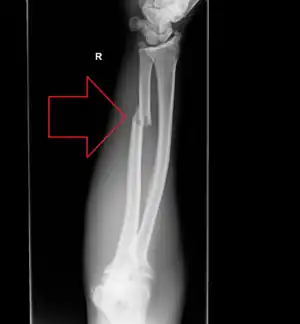

- Monteggia fracture - a fracture of the near to elbow end of the ulna with the dislocation of the head of the radius at the elbow joint.[3]

Monteggia fracture (type of ulna fracture) -

Monteggia fracture (fracture of proximal ulna) -